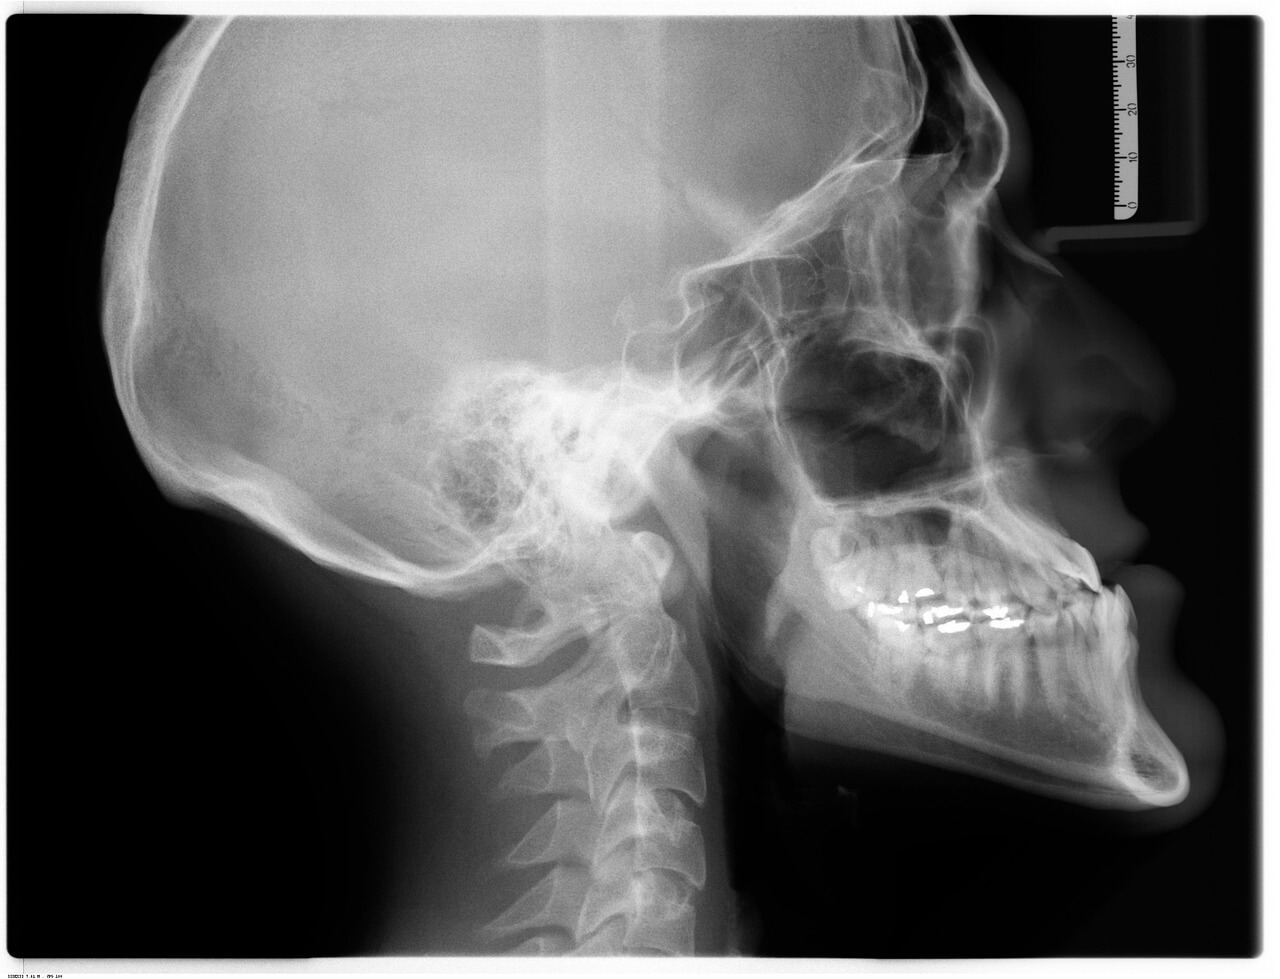

치아교정이 얼굴형까지 바꾼다고?치아교정에 대한 관심이 높아지면서, 단순히 치열을 고르게 만드는 수준을 넘어 “교정을 하면 얼굴형도 달라진다”, 혹은 **“턱선이 정리되고 인상이 부드러워진다”**는 말들을 쉽게 들을 수 있습니다. 실제로 교정 전후 사진을 비교해 보면 눈에 띄게 인상이 부드러워지거나, 턱 돌출이 완화된 듯한 인상을 받는 경우가 많습니다. 그렇다면 정말 교정 치료만으로 얼굴형이 바뀌는 것일까요? 결론부터 말하자면, 치아교정이 얼굴의 형태에 일정 수준의 영향을 미치는 것은 사실입니다. 다만 그 변화의 정도와 방향은 환자의 얼굴 골격 구조, 치아 배열 상태, 교정 방식, 발치 여부, 성장기 여부 등 다양한 요소에 따라 달라지며, 단순히 “교정=얼굴형 변화”로 단정 짓는 것은 지나치게 일반화된 접..